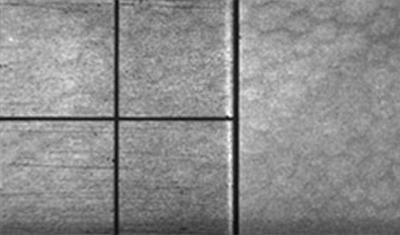

Endoteliografía

Endoteliografía

Siendo la capa más interna de la córnea, está en contacto con el humor acuoso y forma la pared de la cámara anterior; Está compuesta por células hexagonales distribuídas en una sola capa con una cantidad promedio de 2.500-3.000 células por mm2. Van disminuyendo con la edad. Permite el paso de nutrientes al interior de la córnea y controla su estado de deshidratación, siendo por lo tanto la capa responsable de mantener la transparencia corneal. El endotelio tiene muy escasa capacidad de regenerarse por lo que no es capaz de reparar por división un defecto en su extensión, lo cual hace agrandando y extendiendo sus celulas.